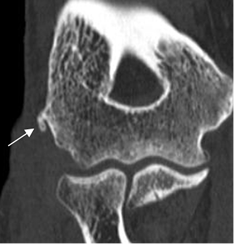

Fig 48. Epicondilitis lateral.

TAC en reconstrucción coronal. Calcificación sobre el origen de los tendones extensores, por inflamación crónica.